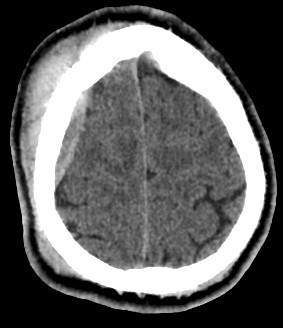

brain CT scan

brain CT scan History

A brain CT scan, also known as a computed tomography scan or CAT scan, is a non-invasive imaging procedure that uses X-rays to create detailed cross-sectional images of the brain and surrounding structures. It's a common diagnostic tool for evaluating head injuries, strokes, brain tumors, and other neurological conditions. Here's a more detailed explanation: What it is: A brain CT scan uses a series of X-ray beams that rotate around the head, capturing multiple images from different angles. These images are then processed by a computer to create detailed cross-sectional views of the brain, allowing doctors to visualize the brain's structures and identify any abnormalities. The scan can be performed with or without contrast dye, which helps to highlight certain tissues and blood vessels for better visualization. Why it's used: Traumatic brain injuries: CT scans are often the first imaging test used to assess the extent of head injuries and identify potential fractures, bleeding, or swelling. Stroke: CT scans can quickly identify whether a stroke is caused by a blood clot (ischemic stroke) or bleeding (hemorrhagic stroke), guiding appropriate treatment. Brain tumors: CT scans can help detect and assess the size and location of brain tumors. Other neurological conditions: CT scans can also be used to diagnose conditions like hydrocephalus (excess fluid in the brain), aneurysms (bulges in blood vessels), and certain types of dementia. Guiding procedures: CT scans can be used to guide biopsies or other procedures involving the brain. What to expect during the procedure: You will lie on a table that slides into the CT scanner, which is a large, doughnut-shaped machine. The scan itself is painless, but some people may experience slight discomfort from lying still on the hard table. If contrast is used, you may feel a warm or flushing sensation, or a metallic taste in your mouth. The scan typically takes only a few minutes. Risks and Precautions: CT scans involve exposure to radiation, but the risk from a single scan is generally considered low. If you are pregnant, it's important to inform your doctor, as alternative imaging methods may be considered to avoid exposing the fetus to radiation. If you have any allergies, particularly to contrast dye, make sure to inform your doctor.